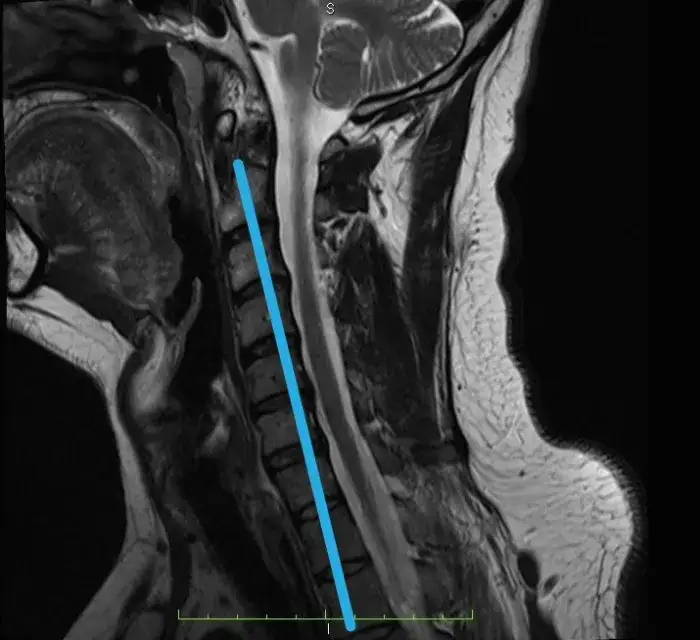

Skręcenie karku: Jak rozpoznać uraz i kiedy na SOR?

Skręcenie karku: poznaj objawy, przyczyny i pierwszą pomoc przy urazie szyi. Dowiedz się, kiedy na SOR i jak wygląda leczenie oraz rehabilitacja.

Ile trwa leczenie skręcenia kręgosłupa szyjnego? Pełny poradnik

Ile trwa leczenie skręcenia kręgosłupa szyjnego? Poznaj konkretne ramy czasowe, etapy rekonwalescencji i czynniki wpływające na powrót do zdrowia.